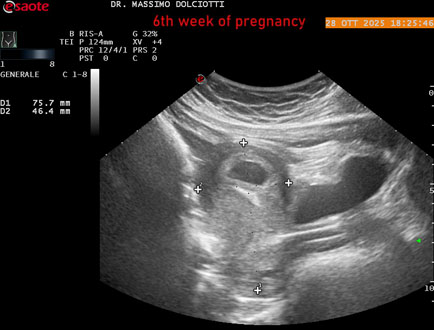

Data inserimento: 29/10/2025

Ecografia del: 28/10/2025

Strumento: Esaote MyLab Eight

Sonda: Convex Multifrequenza 1-8 MHz

Età Paziente: F 35 anni

Motivazione dell'esame: amenorrea.

Commento all'esame: le immagini ed il video documentano in utero il sacco gestazionale, il sacco vitellino e presenza di embrione delle dimensioni di 4,7 mm (CRL), con iniziale attività cardiaca, documentata nel video.

Conclusioni: gravidanza alla 6° settimana di gestazione (pregnancy to the 6th week of gestation).

Presentazione: Dr. Massimo Dolciotti - Ancona

Elaborazione digitale: Andrea Dini - Ancona

VISUALIZZA IL VIDEO